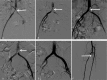

Methods: A 50-year-old female was diagnosed as abdominal aortic saddle embolism, and thrombus aspiration was given immediately via bilateral femoral artery puncture catheter along with artery indwelling catheter thrombolysis.

Results: The saddle embolism was removed completely. After 1-month follow-up, the computed tomography angiography (CTA) examination showed neither stenosis nor thrombus in the abdominal aorta and iliac artery. The patient achieved perfect outcome.